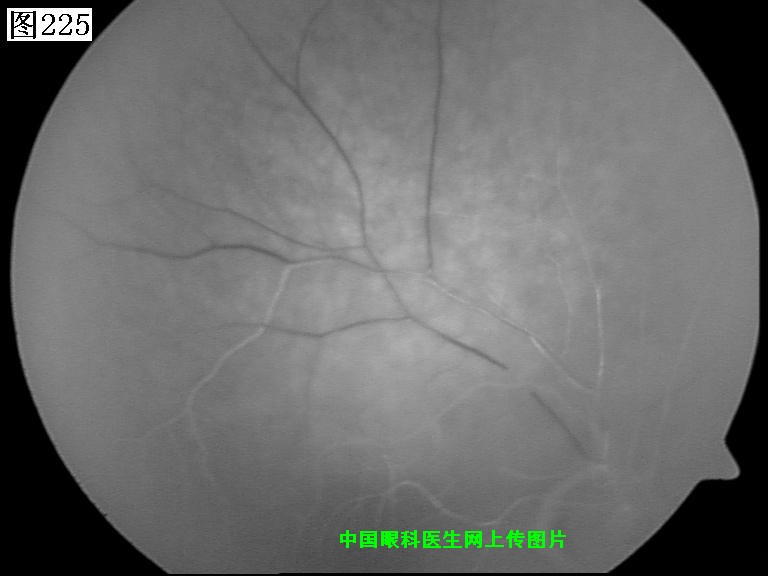

225 226 227 228